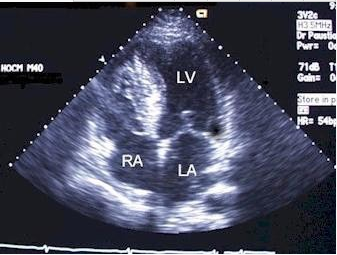

心尖四腔切面,二尖瓣与三尖瓣的鉴别正确的是()。

A:二尖瓣前叶较短

B:二尖瓣位置高

C:三尖瓣位置高

D:三尖瓣隔叶较长

E:三尖瓣前叶较长